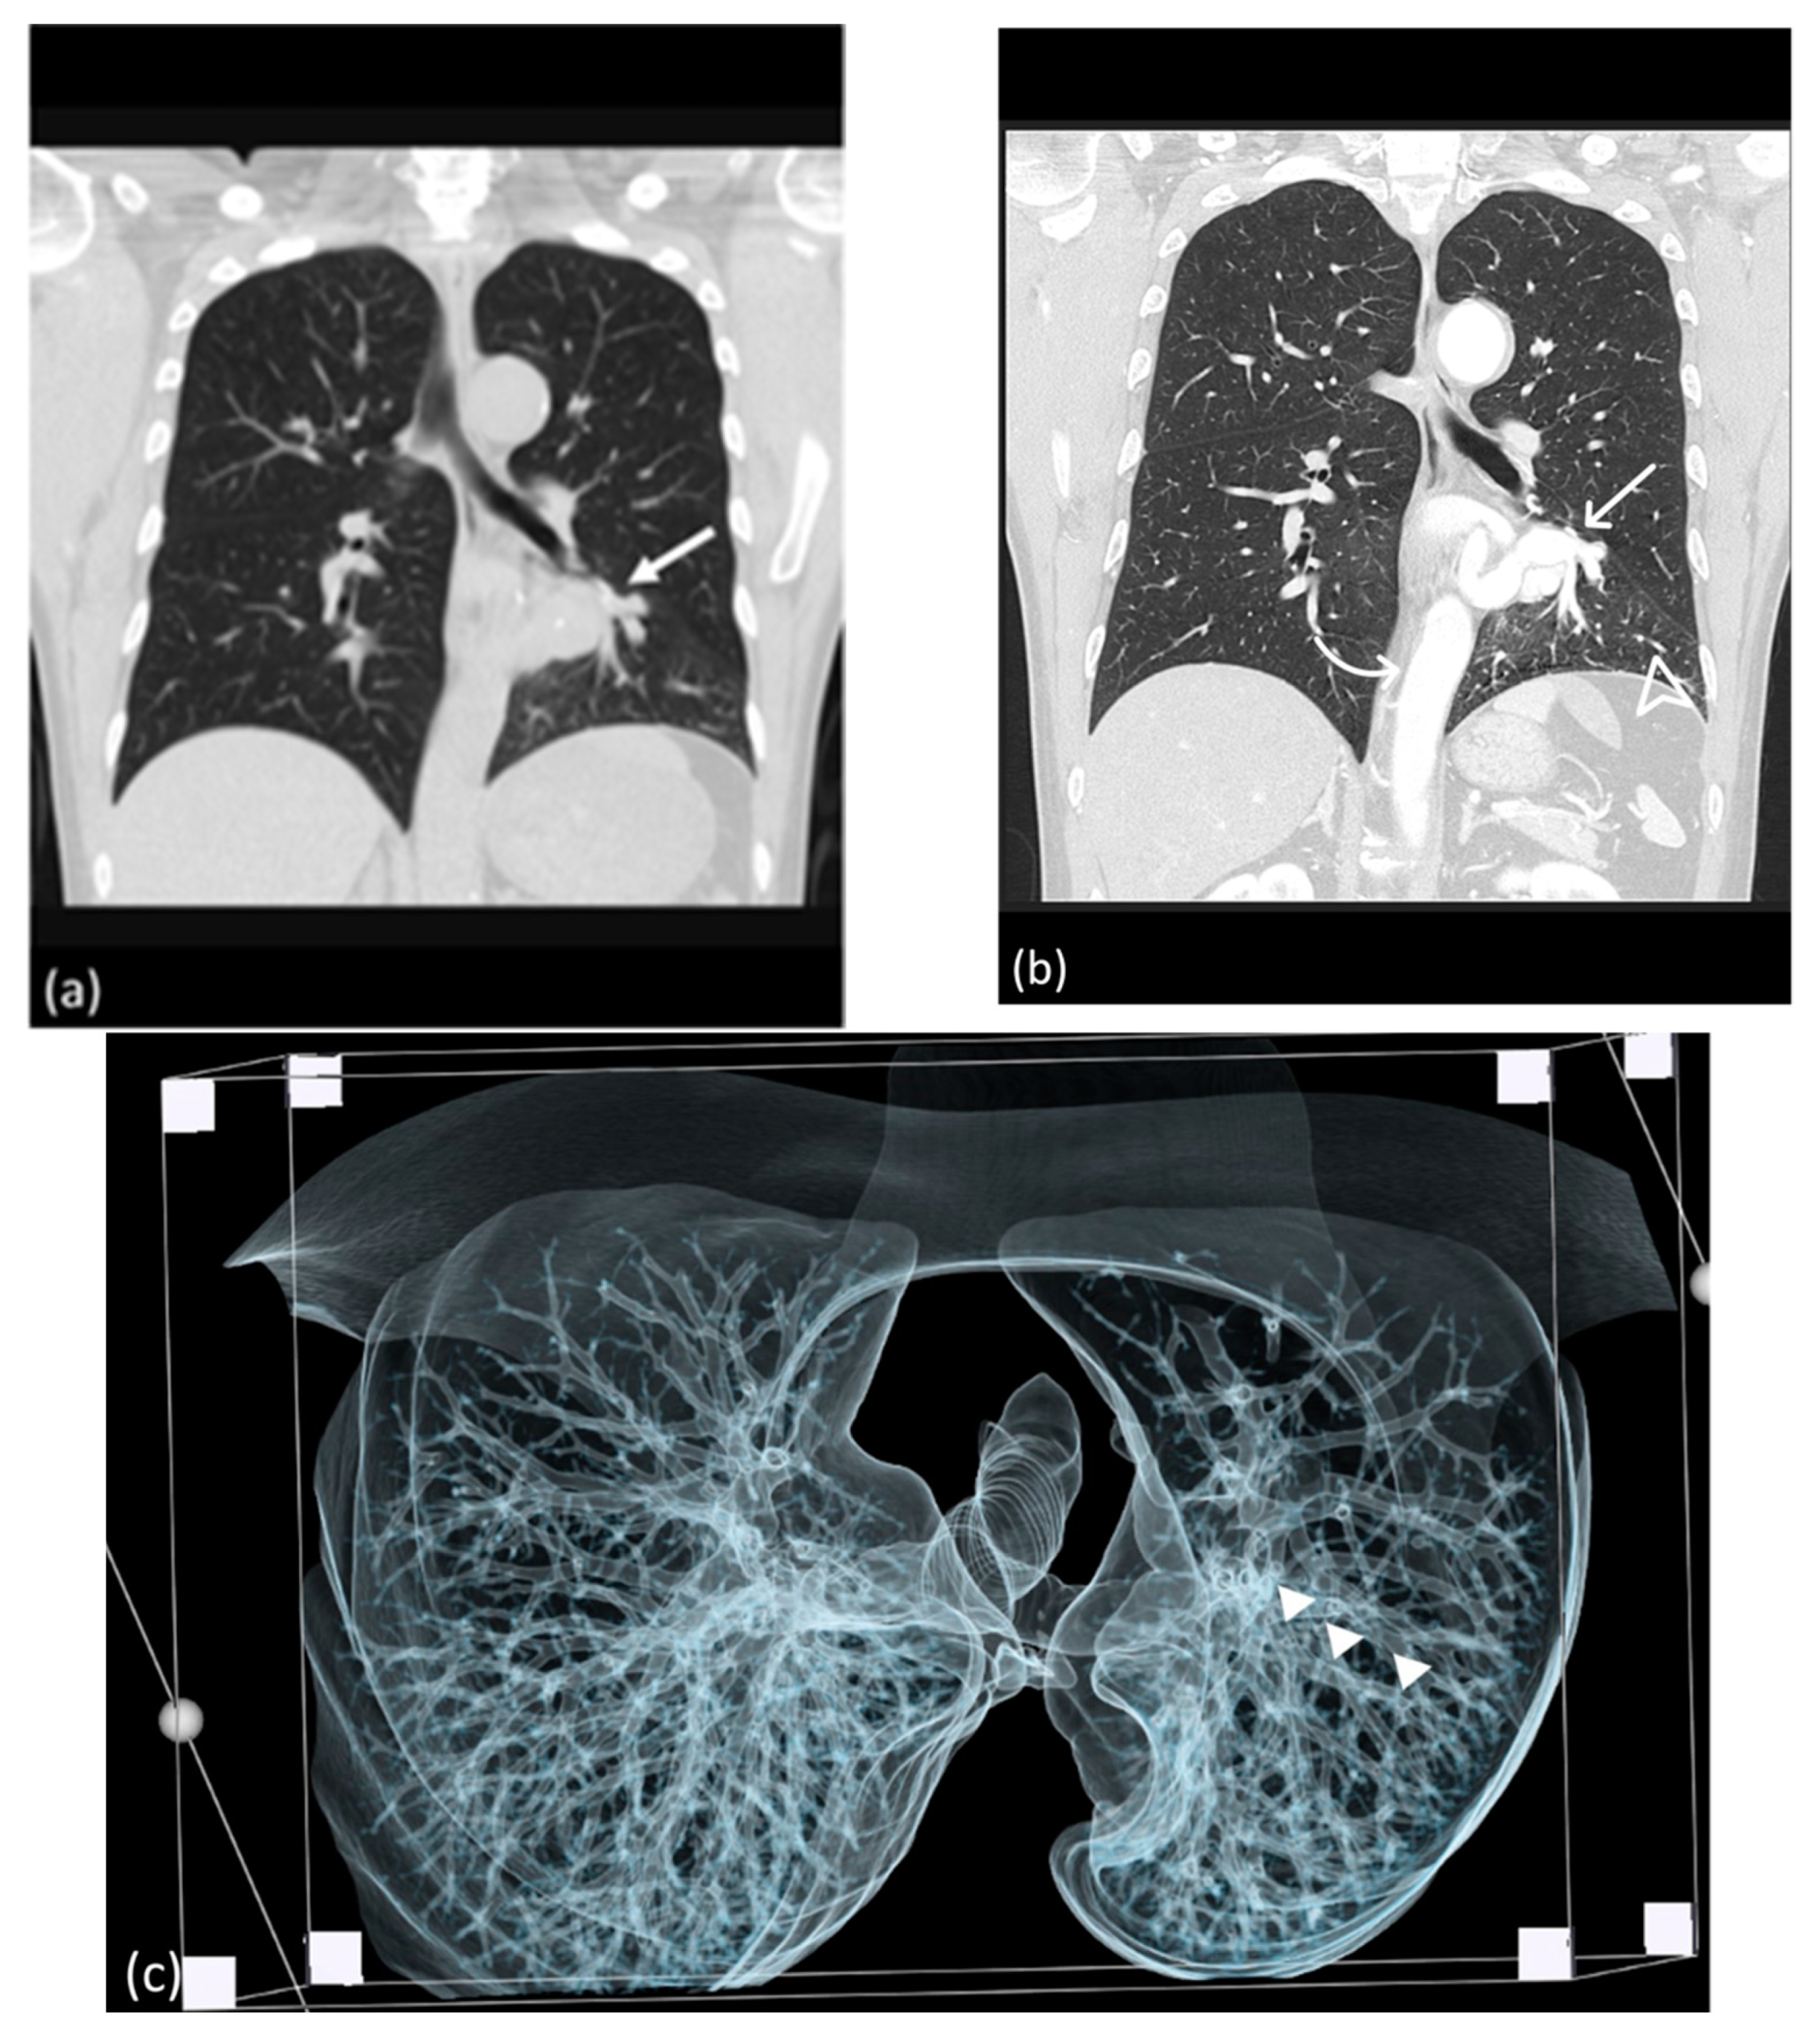

A 51-year-old male patient with no significant medical comorbidities was incidentally discovered to possess a retrocardiac mass after undergoing a chest radiography (Figure 1) during a routine health assessment. Despite the absence of symptoms such as pyrexia, cough, dyspnea, or hemoptysis, the initial impression leaned toward a primary pulmonary neoplasm localized within the left lower lung. Subsequent examinations through CTA (64-slice detector, GE Lightspeed VCT) revealed an enlarged anomalous pulmonary artery originating from the descending thoracic aorta (Figure 2b). Remarkably, the bronchopulmonary distribution within the lung parenchyma remained within normal limits (Figure 2c). As indicated by CTA images, venous drainage returned to the left atrium, and the bronchopulmonary connection was anatomically intact.

Figure 2.

(a) Lesion in the retrocardiac area mimicking lung mass in the non-contrast CT study (arrow). (b) Aberrant systemic artery (arrow) originating from the thoracic aorta (curve arrow), supplying the left lower lung, as revealed by CTA; the bronchovascular marking of the left lower lobe is prominent in the lung window of the CTA (arrowhead). (c) CT volume rendering indicating the continuity of the bronchogram from caudal to cranial; the bronchopulmonary tract is patent and continuously (arrowhead) connected to the main bronchus in volumetric rendering of the caudal-cranial view.